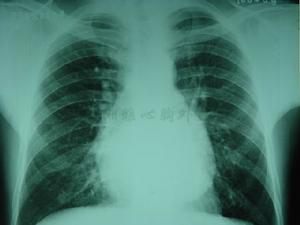

原發性縱隔感染早期診斷較為困難,一般症狀有胸前疼痛、低熱、全身無力、體重下降、咳嗽,呈慢性病的污泥生症狀,甚至發展成惡病質化驗可發現有血紅蛋白的降低,白細胞持續升高,X線攝片早期不能發現異常當發現局限的肉芽腫型縱隔感染,X線片上產生局部縱隔影增寬。最常見的X線表現為右氣管旁腫塊突出,並有胸骨後間隙密度增高,病灶由肉芽腫塊、炎症淋巴對、纖維組織混合。隆突下區有相似之腫塊於側位及斜信片上最易察見。如感染侵蝕後縱隔間隙,侵犯食管緣時,食管造影片可見局限性邊緣不整從後前位胸片上觀察隆突下腫塊僅僅是心影上部密度增高。大的腫塊使雙側主支氣管移位氣管隆突分叉角增寬腫塊輪廓不會十分具體清晰。如腫塊中心壞死或乾酷樣變,則容易鈣化鈣化灶之輪廓多不規則,斷層攝影(CT)可以顯示。局限性纖維性變型X線診斷,以縱隔內某一器官之X線影像為突出,特別常見者為上腔靜脈綜合徵右上縱隔影增寬為突出。梗阻位於上腔靜脈入口以下時,上腔靜脈血管成為主側支通路而擴大,在右支氣管角處顯示局部擴張肺動脈狹窄顯示肺野供血少及右心室肥大。肺靜脈狹窄由於回流障礙而肺野充血。廣泛纖維型縱隔感染,縱隔變硬,邊緣銳利失去正常曲度,雙側縱隔影變硬及毛糙。如是慢性縱隔膿腫繼發於椎體感染,腫塊影向雙側縱隔凸出骨結核引起的縱隔膿腫在X線片上常可以看見。